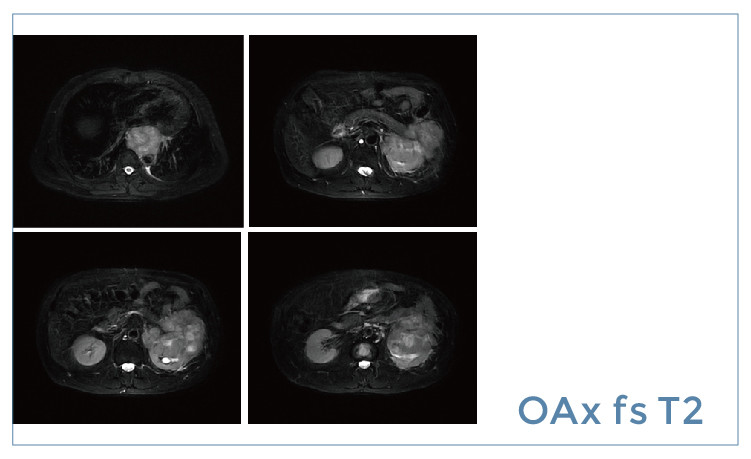

【朗润影像档案】磁共振影像病例分享(编号20190510)